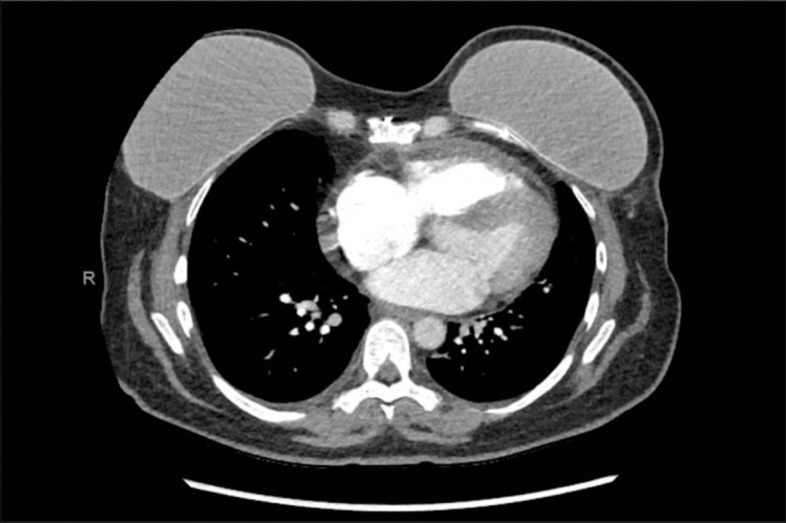

She presented with left-sided pleuritic sternal pain on 6/6/2021. She was recently started on proton radiation therapy on 5/25/2021 and had received 18 Gy of planned 50 Gy. Her chest pain was 5/10, worse with deep inspiration, and not alleviated with 200 mg ibuprofen and then 600 mg ibuprofen. She was referred to see her cardiology team 6/10/2021. Electrocardiogram (ECG) showed normal sinus rhythm with low voltage in limb leads with no ST changes or PR depression. Given her pleuritic pain and history of cancer, D-dimer was ordered and was slightly elevated at 0.77. CT chest was negative for any acute pulmonary embolism. Trace pericardial fluid was seen on the CT scan (Fig. 1) which was further evaluated with a repeat echocardiogram that showed a trivial pericardial effusion with no evidence of tamponade (Fig. 2). Her prior echocardiogram 6 months ago showed no evidence of pericardial effusion. Her ESR and CRP were significantly elevated at 38 and 145 respectively. The etiology of her chest pain was deemed to be secondary to pericarditis induced by proton beam therapy. While there was consideration that her chemotherapy regimen could have caused her pericarditis, the timeline and presentation of her symptoms were more likely due to the proton beam therapy as the precipitating cause. She was started on ibuprofen 800 mg three times a day with a scheduled taper. The patient continued to have persistent chest pain and was started on colchicine 0.6 mg daily with full resolution of her symptoms within a month.

Fig. 1.

Chest CT showing mild pericardial effusion, no evidence of inflammation or cardiomyopathy